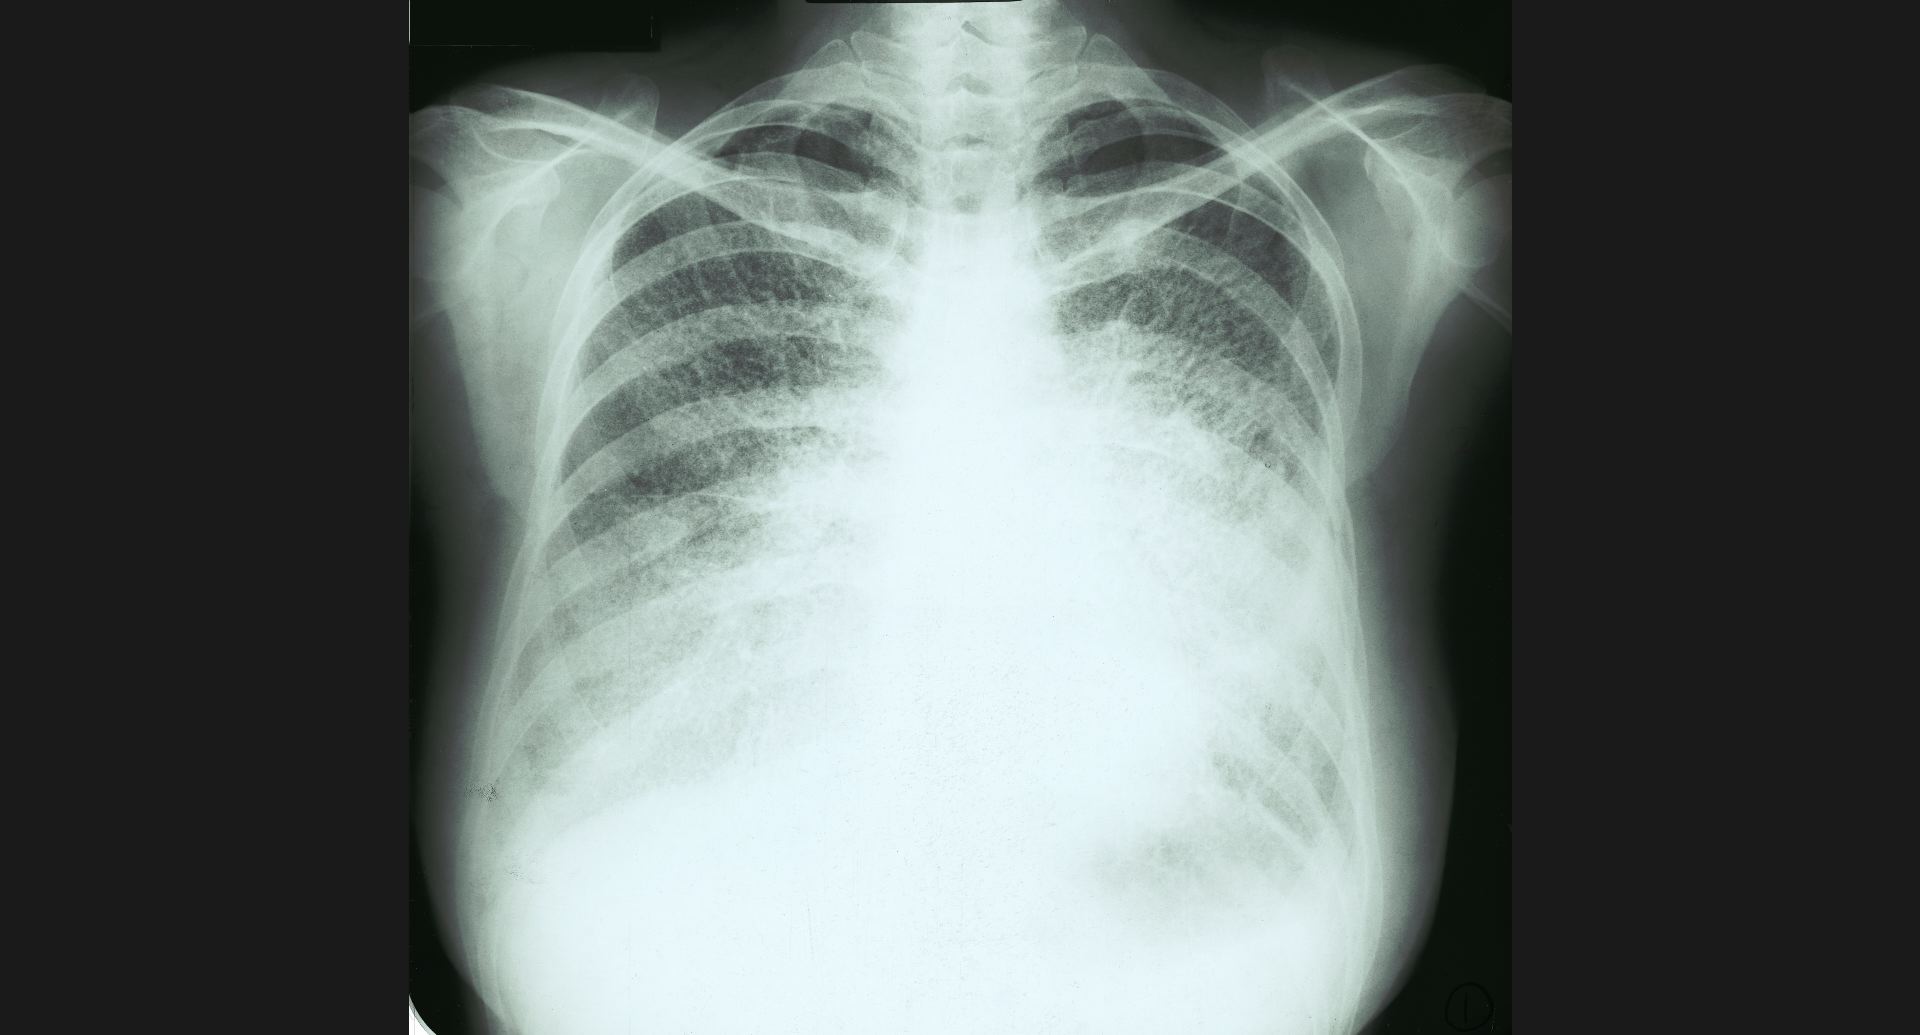

fig.9(94KB) :Pneumoconiosis

細かい斑状陰影。